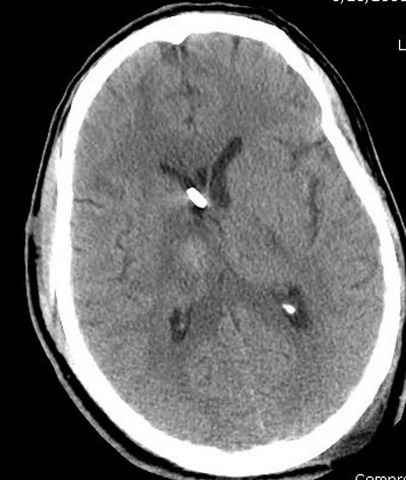

Наблюдается службой травмы и нейрохирургии (ICP) Increased Intracranial Pressure by ventricular cateter

больной без сознания, со слов нейрохирурга, наблюдается положительная динамика в нейрохирургическом статусе.

-Согласен, рана до прихода пластического хирурга была 38х13 см, можно было постараться закрыть сверху, а в нижнем отделе где был ожог, применить кожную пластику меньшим размером. К моему удивлению и разочарованию, когда вернулся из другой операционной (шли пареллельные операции), он уже успешно заканчивал свое дело. Кстати недавно разговаривал с нейрохирургом, он снял ICP (intracranial prеssure monitor), внутричерепное давление стабилизировалось, ортопеды и хирурги закончили с лечением, теперь длительное неврологическое восстановление.

Было множество случаев, когда безнадежные больные с повреждением головного мозга через пару месяц приходили в сознание, поэтому уделяем внимание на ургентность стабилизации переломов костей скелета.